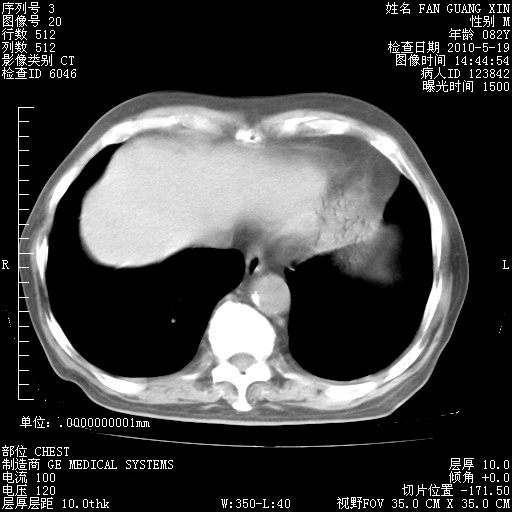

治疗3周后的肺部CT纵隔窗

再治疗10天后的肺部CT